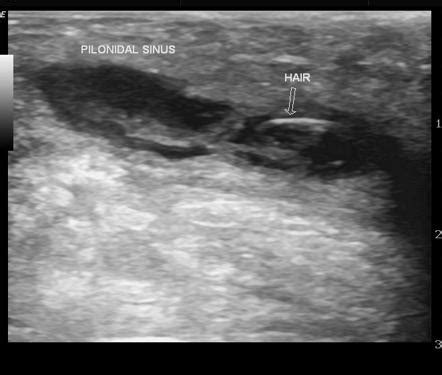

When it comes to imaging a pilonidal abscess , ultrasound is often the first tool in the radiologist’s toolkit, and for good reason, guys. It’s readily available, relatively inexpensive, and provides excellent real-time visualization of soft tissues, making it fantastic for detecting fluid collections like those pesky abscesses. The way ultrasound works is by bouncing sound waves off your body’s tissues and then interpreting the echoes to create an image. For a pilonidal abscess, the sonographer will use a transducer, which is like a wand, and apply a gel to the skin over the affected area. This gel helps to get good contact and transmit the sound waves effectively. As they move the transducer around, they’ll be looking for specific signs. The abscess itself typically appears as a well-defined, anechoic or hypoechoic area – basically, a dark or grayish area on the ultrasound screen, indicating a fluid-filled space. You might also see thickened walls around this collection, which signifies the body’s inflammatory response. The beauty of ultrasound is its ability to differentiate between solid and cystic structures. So, it can confirm that what they’re seeing is indeed an abscess filled with pus, rather than a solid tumor or other mass. Furthermore, ultrasound can help assess the size of the abscess, its depth, and its relationship to nearby structures, like muscles or blood vessels. This information is crucial for surgical planning, helping the surgeon decide on the best approach for drainage or excision. In some cases, ultrasound can even be used during the drainage procedure, guiding the needle precisely into the abscess cavity to ensure complete evacuation of the pus. This real-time guidance is a huge advantage. While ultrasound is great, it’s important to remember that it’s highly dependent on the skill of the sonographer and can sometimes be limited in obese patients or if there’s a lot of gas in the bowel overlying the area. But generally speaking, for initial evaluation and confirmation of a pilonidal abscess, ultrasound is a true workhorse in the radiology department.